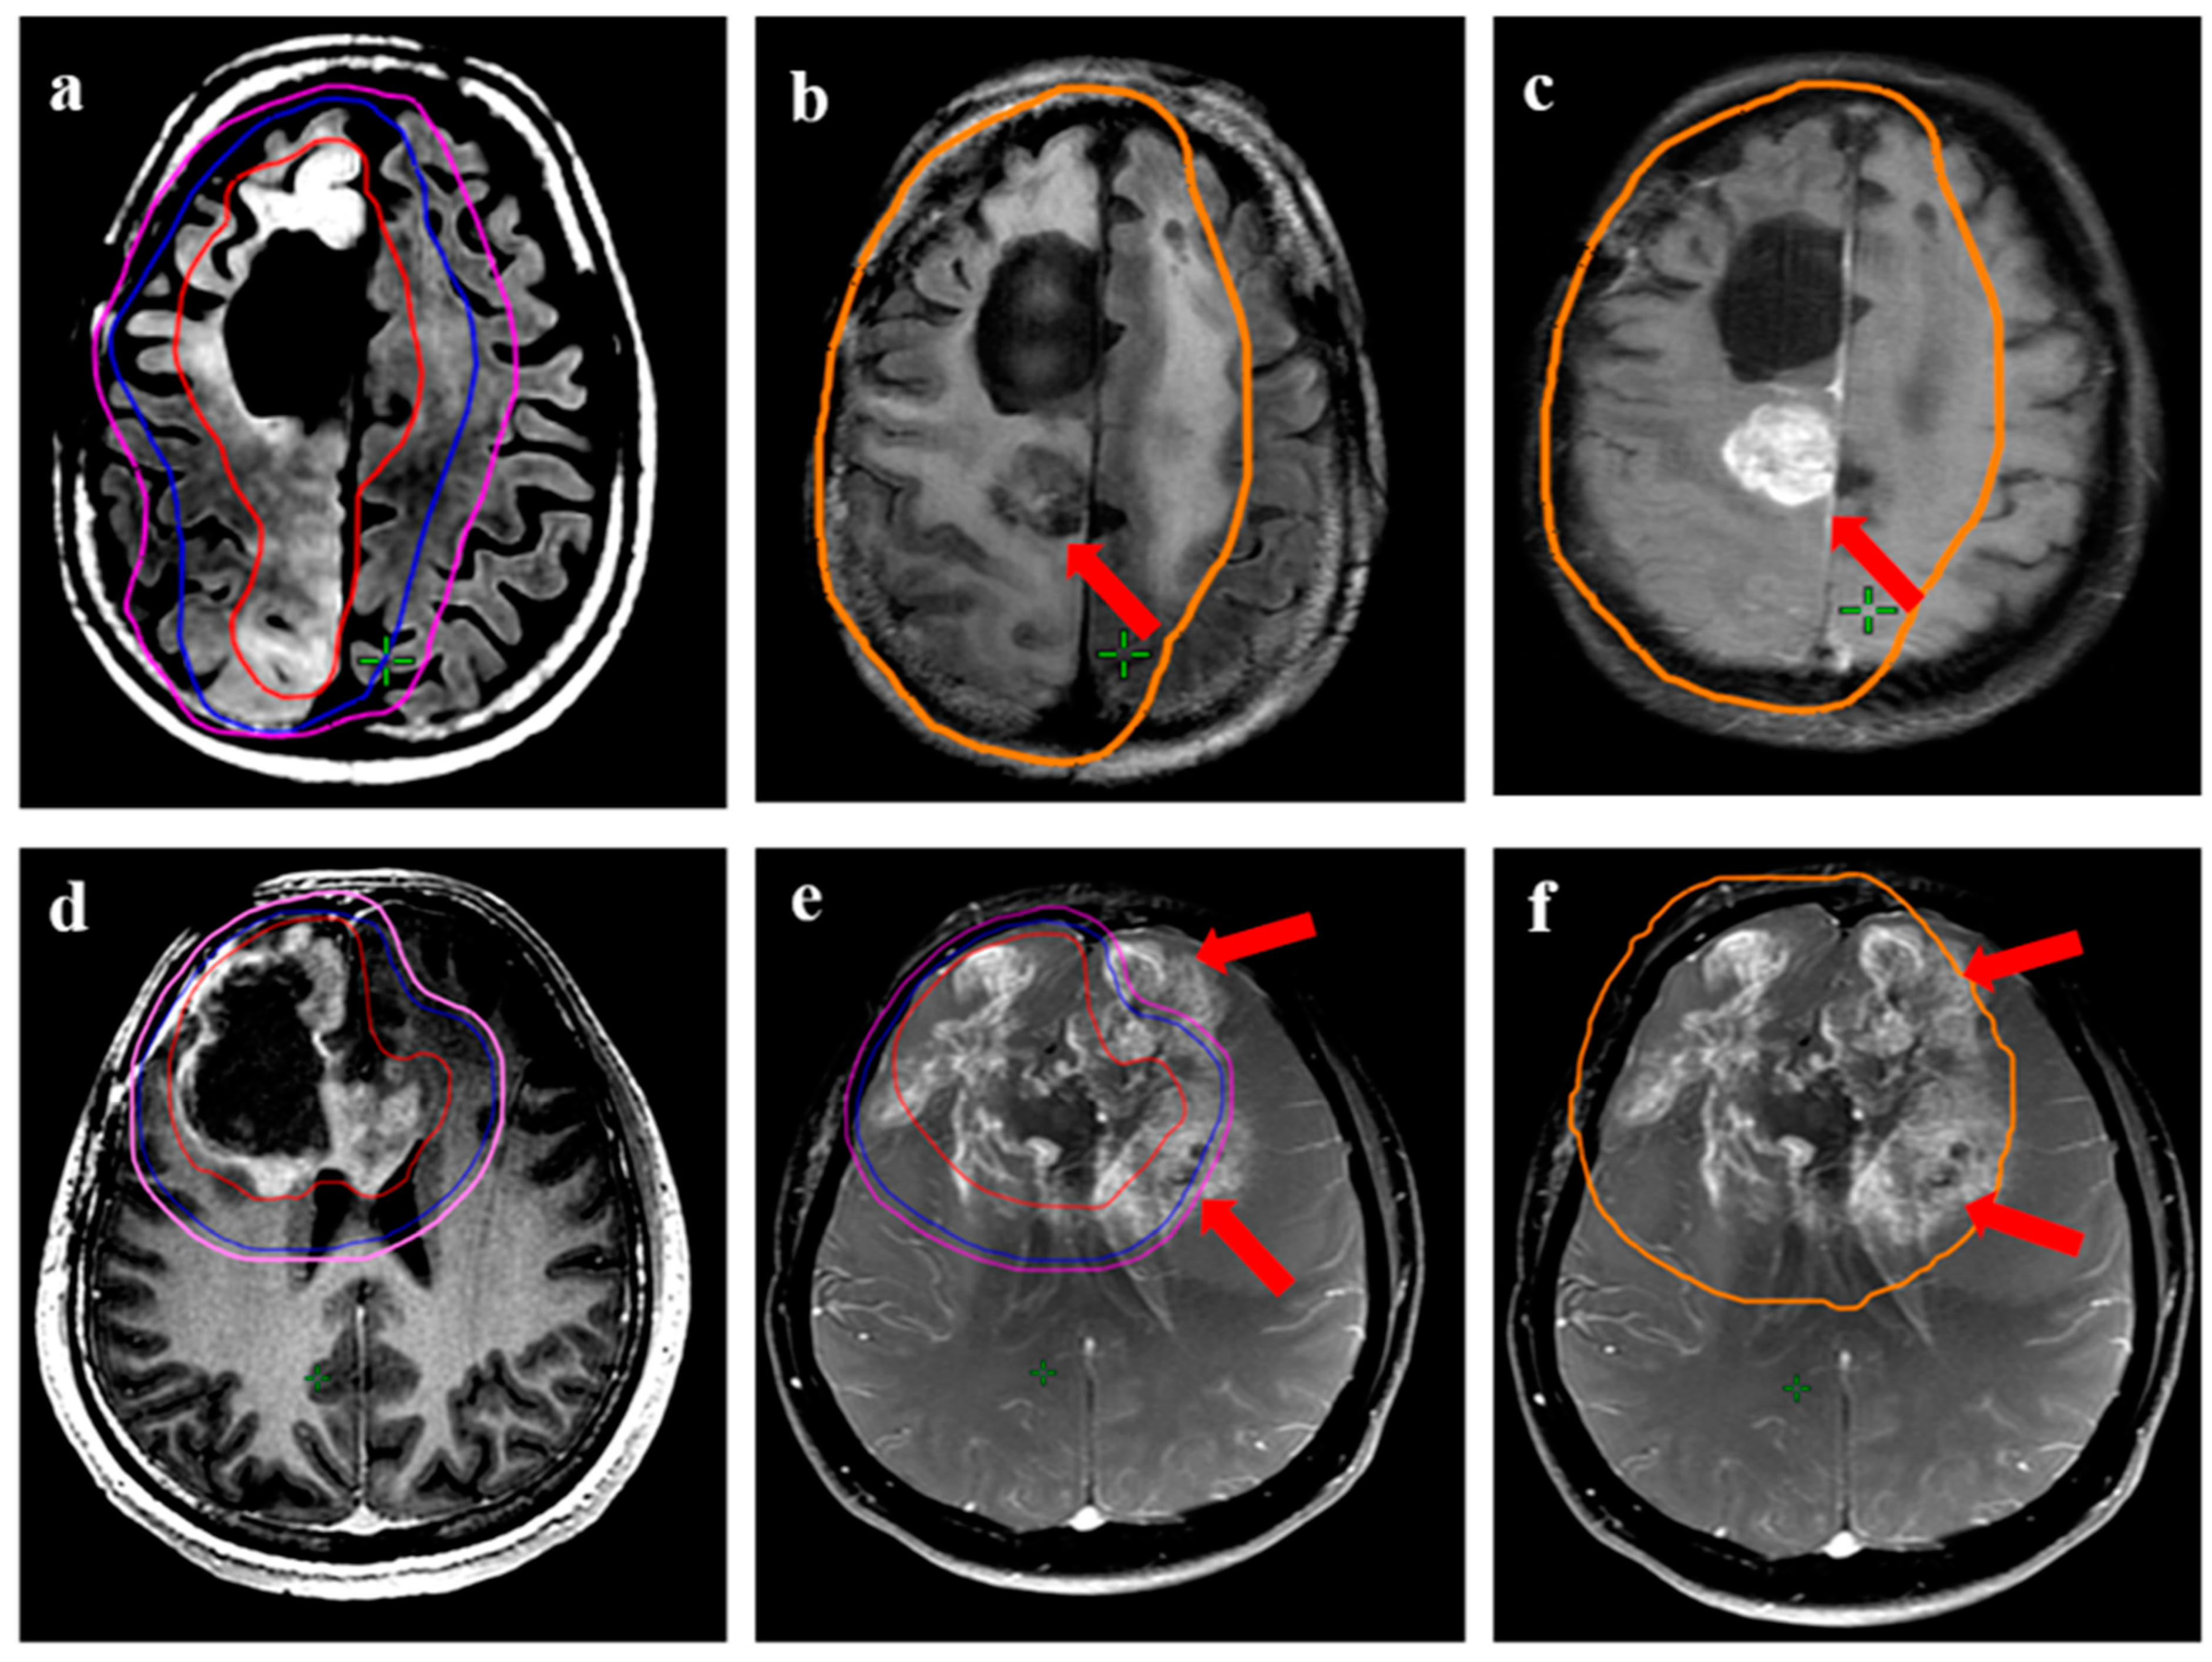

Figure 6.

Demonstration of marginal recurrence following re-irradiation for a 43-year female with transformed high-grade glioma. (a) shows the target volumes (GTV: red, CTV: blue; PTV: magenta) on T1w contrast MRI. The GTV was the enhancing disease, with CTV drawn as an expansion of 10 mm around the enhancing disease. (b,c) demonstrates recurrent disease (arrows) with respect to target volumes and 95% isodose line (orange), 1. (d) is a representation from lower axial slices showing the growth of recurrent disease further beyond the 95% isodose line.

Figure 7.

Distant relapse following re-irradiation in a 38-year male with IDH-mutant astrocytoma with transformation (radiological) to grade 4 during reirradiation. (a,b) show the target volumes (GTV: red, CTV: blue; PTV: magenta) on T1w contrast and T2w images. The GTV encompassed all the T2w altered signals, including the enhancing disease, while CTV was 10–15 mm expansion along the brain parenchyma. (c) represents the response in the primary re-irradiated region 6 months following ReRT, while the lower panel shows axial (d), coronal (e), and sagittal (f) T1w contrast MRI from the same time-point demonstrating distant areas of recurrent disease (arrow) beyond the 95% isodose line (orange).